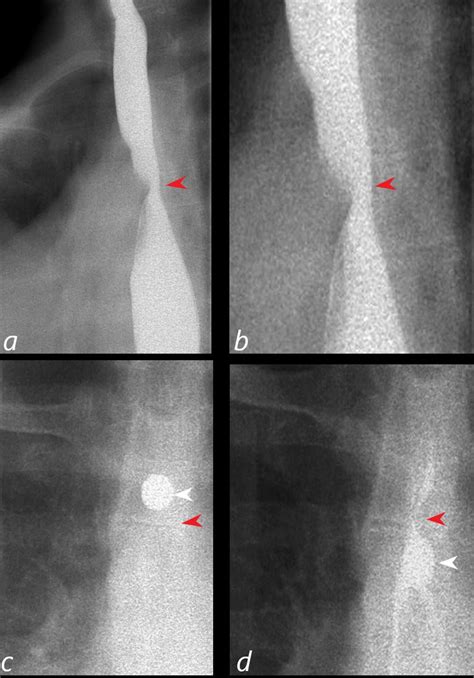

Barium Swallow Study Useful for identifying an esophageal impression or indentation.

When an aberrant vessel is suspected, clinicians rely on non-invasive imaging techniques to map the vascular architecture. These diagnostic tools are critical for determining the path of the artery and its relationship to surrounding structures.

Imaging Modality Primary Benefit

Computed Tomography (CT) Angiography Provides highly detailed 3D reconstructions of vascular anatomy.

Magnetic Resonance (MR) Angiography Excellent for soft tissue visualization without radiation exposure.

Doppler Ultrasound Can assess flow characteristics, though limited in deep thoracic structures.